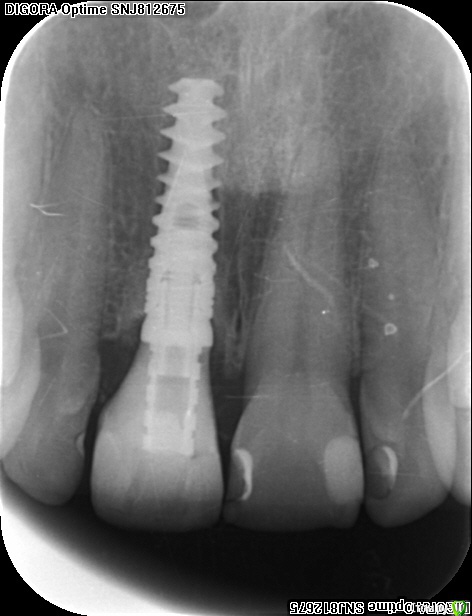

Популярный пост an_ver Опубликовано 15 января, 2016 Популярный пост Поделиться Опубликовано 15 января, 2016 11,жил долго и счастливо..но тут Новый год(((, скол ниже уровня ЦЭС на 3 мм...от экструзии отказалась.Из своего зуба сколхозил шаблон,чтоб наверняка. Удалил,кюретаж,вестибулярка целая, SPI 4.2*13 мм,с бугра ССТ,на всякий)),в щели Апатос,врем.абатмент,врем.коронка из своего зуба. 1ч.20мин.)) 27 Ссылка на комментарий

an_ver Опубликовано 16 января, 2016 Автор Поделиться Опубликовано 16 января, 2016 Клёво!!!Можно вопрос: как сст всовывали ?Просто опыта в этом аспекте очень мало и понятие "в щели" не совсем понятно.СпасибоВ щели: это свободные обьем лунки,после установки импланта,т.е. все пустоту забиваем графтом (Апатос). По ССТ: скальпель 15С, параллельно кости осторожно,маятниковыми движениями,до уровня прикрепления или глубже формируете карман,вкол с вестибулярки-выкол в лунке,вкол в сст,выкол там же,далее вкол внутри кармана и затягиваете сст...но проще посмотреть...сейчас А.Смолякова по рецессии выложила видео,принцип такой же 2 Ссылка на комментарий